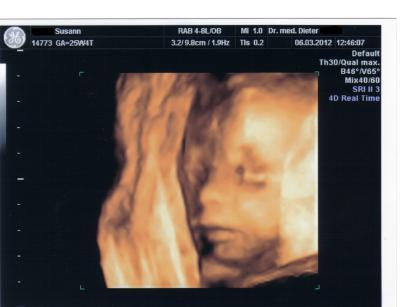

Also es ist alles in Ordnung es war so wunderschön 30 ganze Minuten BabyTv . Es bleibt bei einem Prinzen er ist ca 32 cm Große und 604 Gramm "leicht". er wollte sich nicht so zeigen wie er sollte aber am Anfang haben wir ein schönes Bild hinbekommen. Ich bin noch mehr Verliebt als Vorher so hänge euch noch Bilder ran lg

es ist wirklich unglaublich wie unsere zwerge sich verbiegen können mein prinz hatte eine hand und einen Fuß im Gesicht und hat am Fuß gelutscht es war wirklich unglaublich